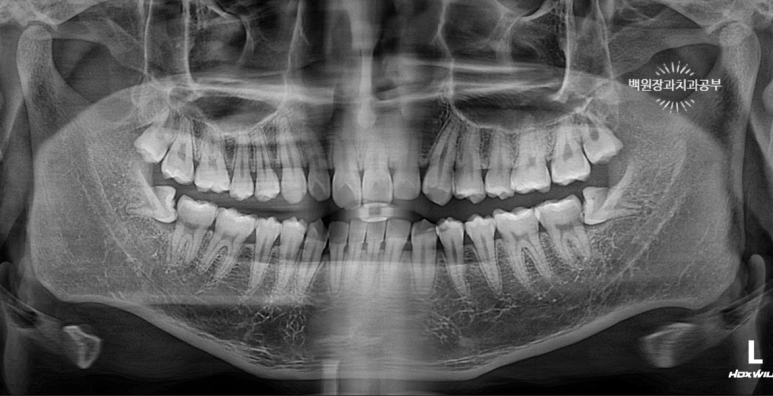

21세 남자 환자였습니다. 양쪽 아래 매복 사랑니가 존재하는 상태였어요.

수평 매복 상태 (horizontal partial impacted state) 였으며, 딱 봐도 뽑아야될 것 같아요!!

노란색 원으로 표시된 치아들이 위 사랑니 입니다. 상악 제3대구치라고도 불러요.

빨간색 원으로 표시된 치아들은 아래 사랑니 입니다. 하악 제3대구치라고도 불러요.